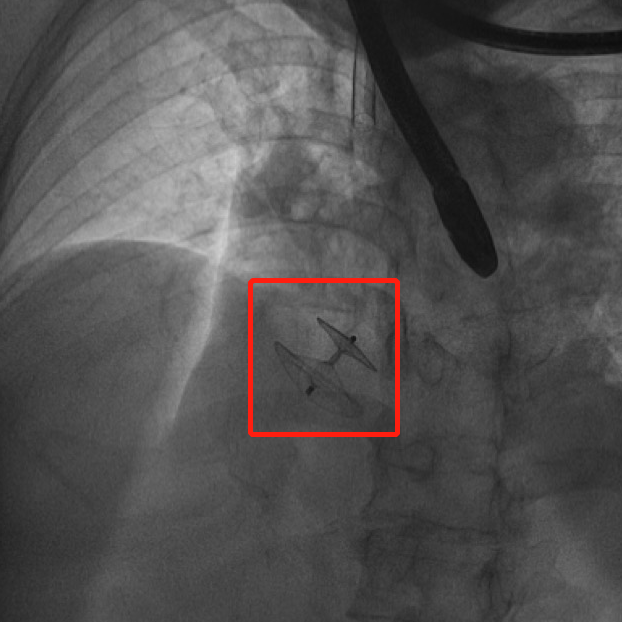

食道超声实时监测下,耿召华教授精细操作,经股静脉穿刺顺利送入导丝,由导丝引导送入尺寸最大的封闭器(25-35 毫米),通过卵圆孔后,逐一释放两侧封堵伞,直至固定良好,无残余分流,手术顺利完成。